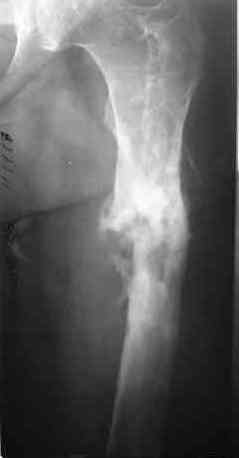

После нескольких некрэктомий, проведения аутодермопластики и заживдения ожоговой раны через 2 месяца после травмы произведен открытый остеосинтез левой бедренной кости штифтом и пластиной (деротационной) [image 01, 02]. Через 1 год и 7 месяцев после травмы у больного диагностированы ложный сустав и хронический остеомиелит левой бедренной кости. Произведено удаление металлических фиксаторов, секвестрэктомия и остеосинтез бедренной костивнешним двухплоскостным стержневым аппаратом [image 03, 04] .